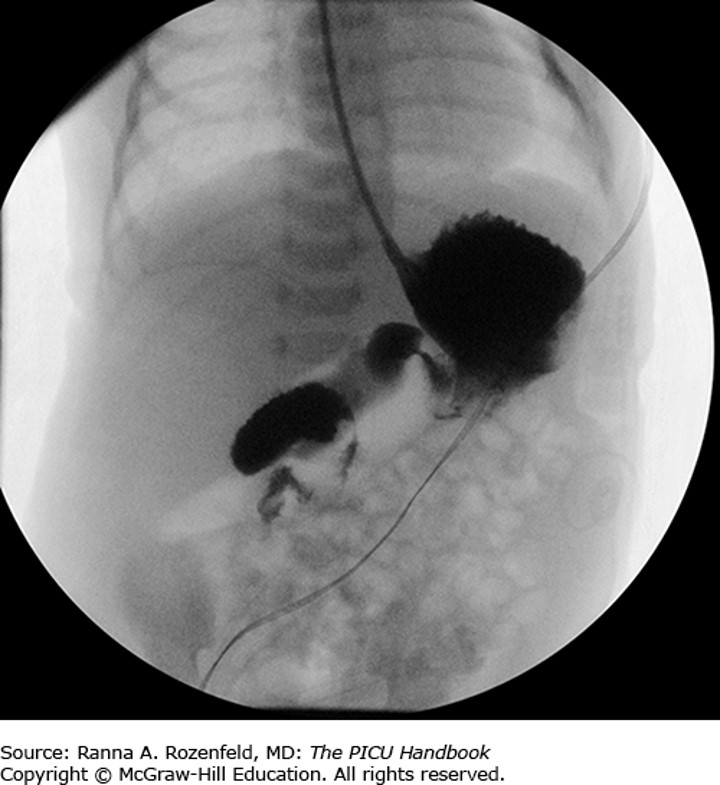

The correct answer is “B.” This infant has malrotation with volvulus—a surgical emergency. Rotational anomalies may become symptomatic at any age; however, more than 80% present in the first month of life, often in the first week. Risk of acute volvulus is highest in the neonatal period. In malrotation, the intestine fails to rotate in utero and fixate in the correct position. It is adhered by a narrow pedicle of mesentery, which allows the intestine to twist around itself. The cecum ends up in the right upper quadrant. The risk is volvulus, most often at midgut. This occurs when the intestine strangulates by twisting, cutting off the blood supply and blocking the flow of fecal contents and gas through the tract. Bad outcomes (perforation, infarction) ensue if it is not surgically corrected. (You may have heard the term Ladd bands used. These are tissue bands that cross and obstruct the duodenum). Any infant who presents with bilious emesis is an emergency case. There is also an atypical presentation. (Are you surprised?) Intermittent twisting with pain and vomiting may occur in older children. It is frequently misdiagnosed as cyclic vomiting.

Photo: Chapter 64 GI Emergencies, Rozenfeld RA. The PICU Handbook; 2018.